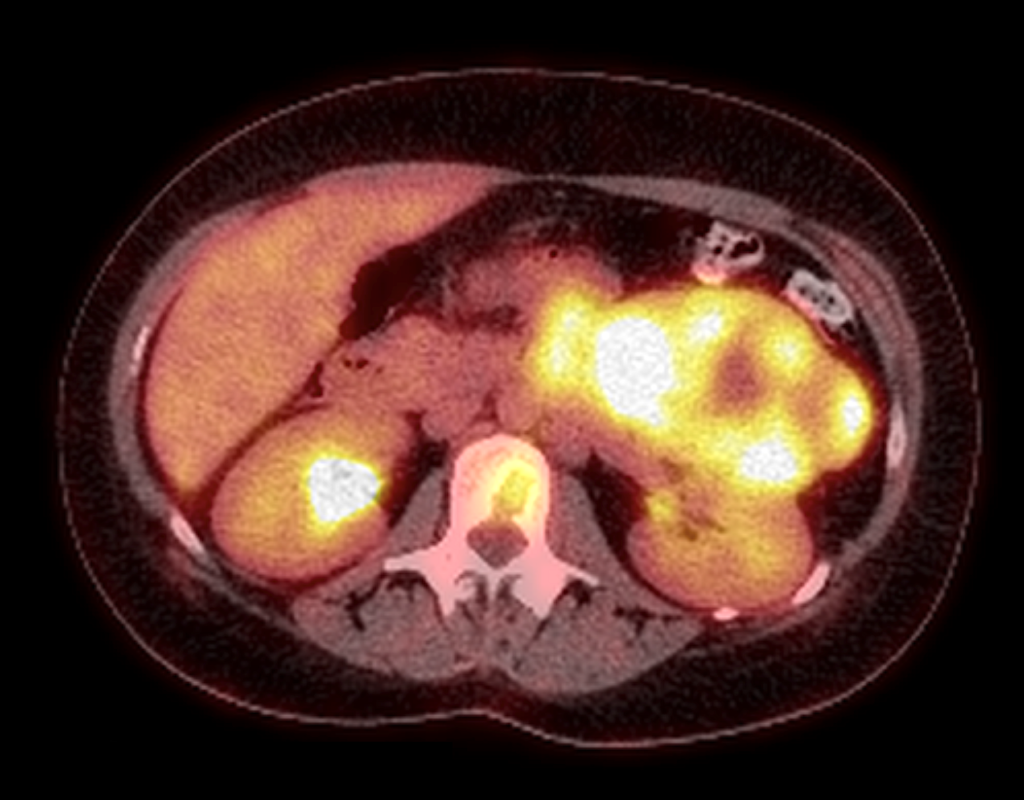

- τομογραφία εκπομπής ποζιτρονίων (PET Scan), για την επιβεβαίωση ή τον αποκλεισμό της παρουσίας απομακρυσμένων μεταστάσεων σε άλλα όργανα.

PET Scan (PET/CT) σε ασθενή μας με καρκίνο του αριστερού επινεφριδίου, το οποίο επιβεβαιώνει την έντονη καθήλωση του ραδιοφαρμάκου στην ανατομική περιοχή του αριστερού επινεφριδίου.